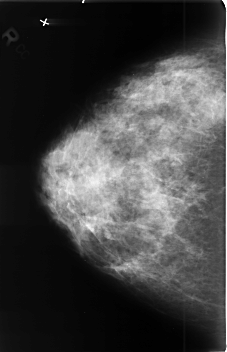

B_3409_1.RIGHT_MLO

RIGHT_MLO LINES 4544 PIXELS_PER_LINE 2800 BITS_PER_PIXEL 12 RESOLUTION 50 NON_OVERLAY